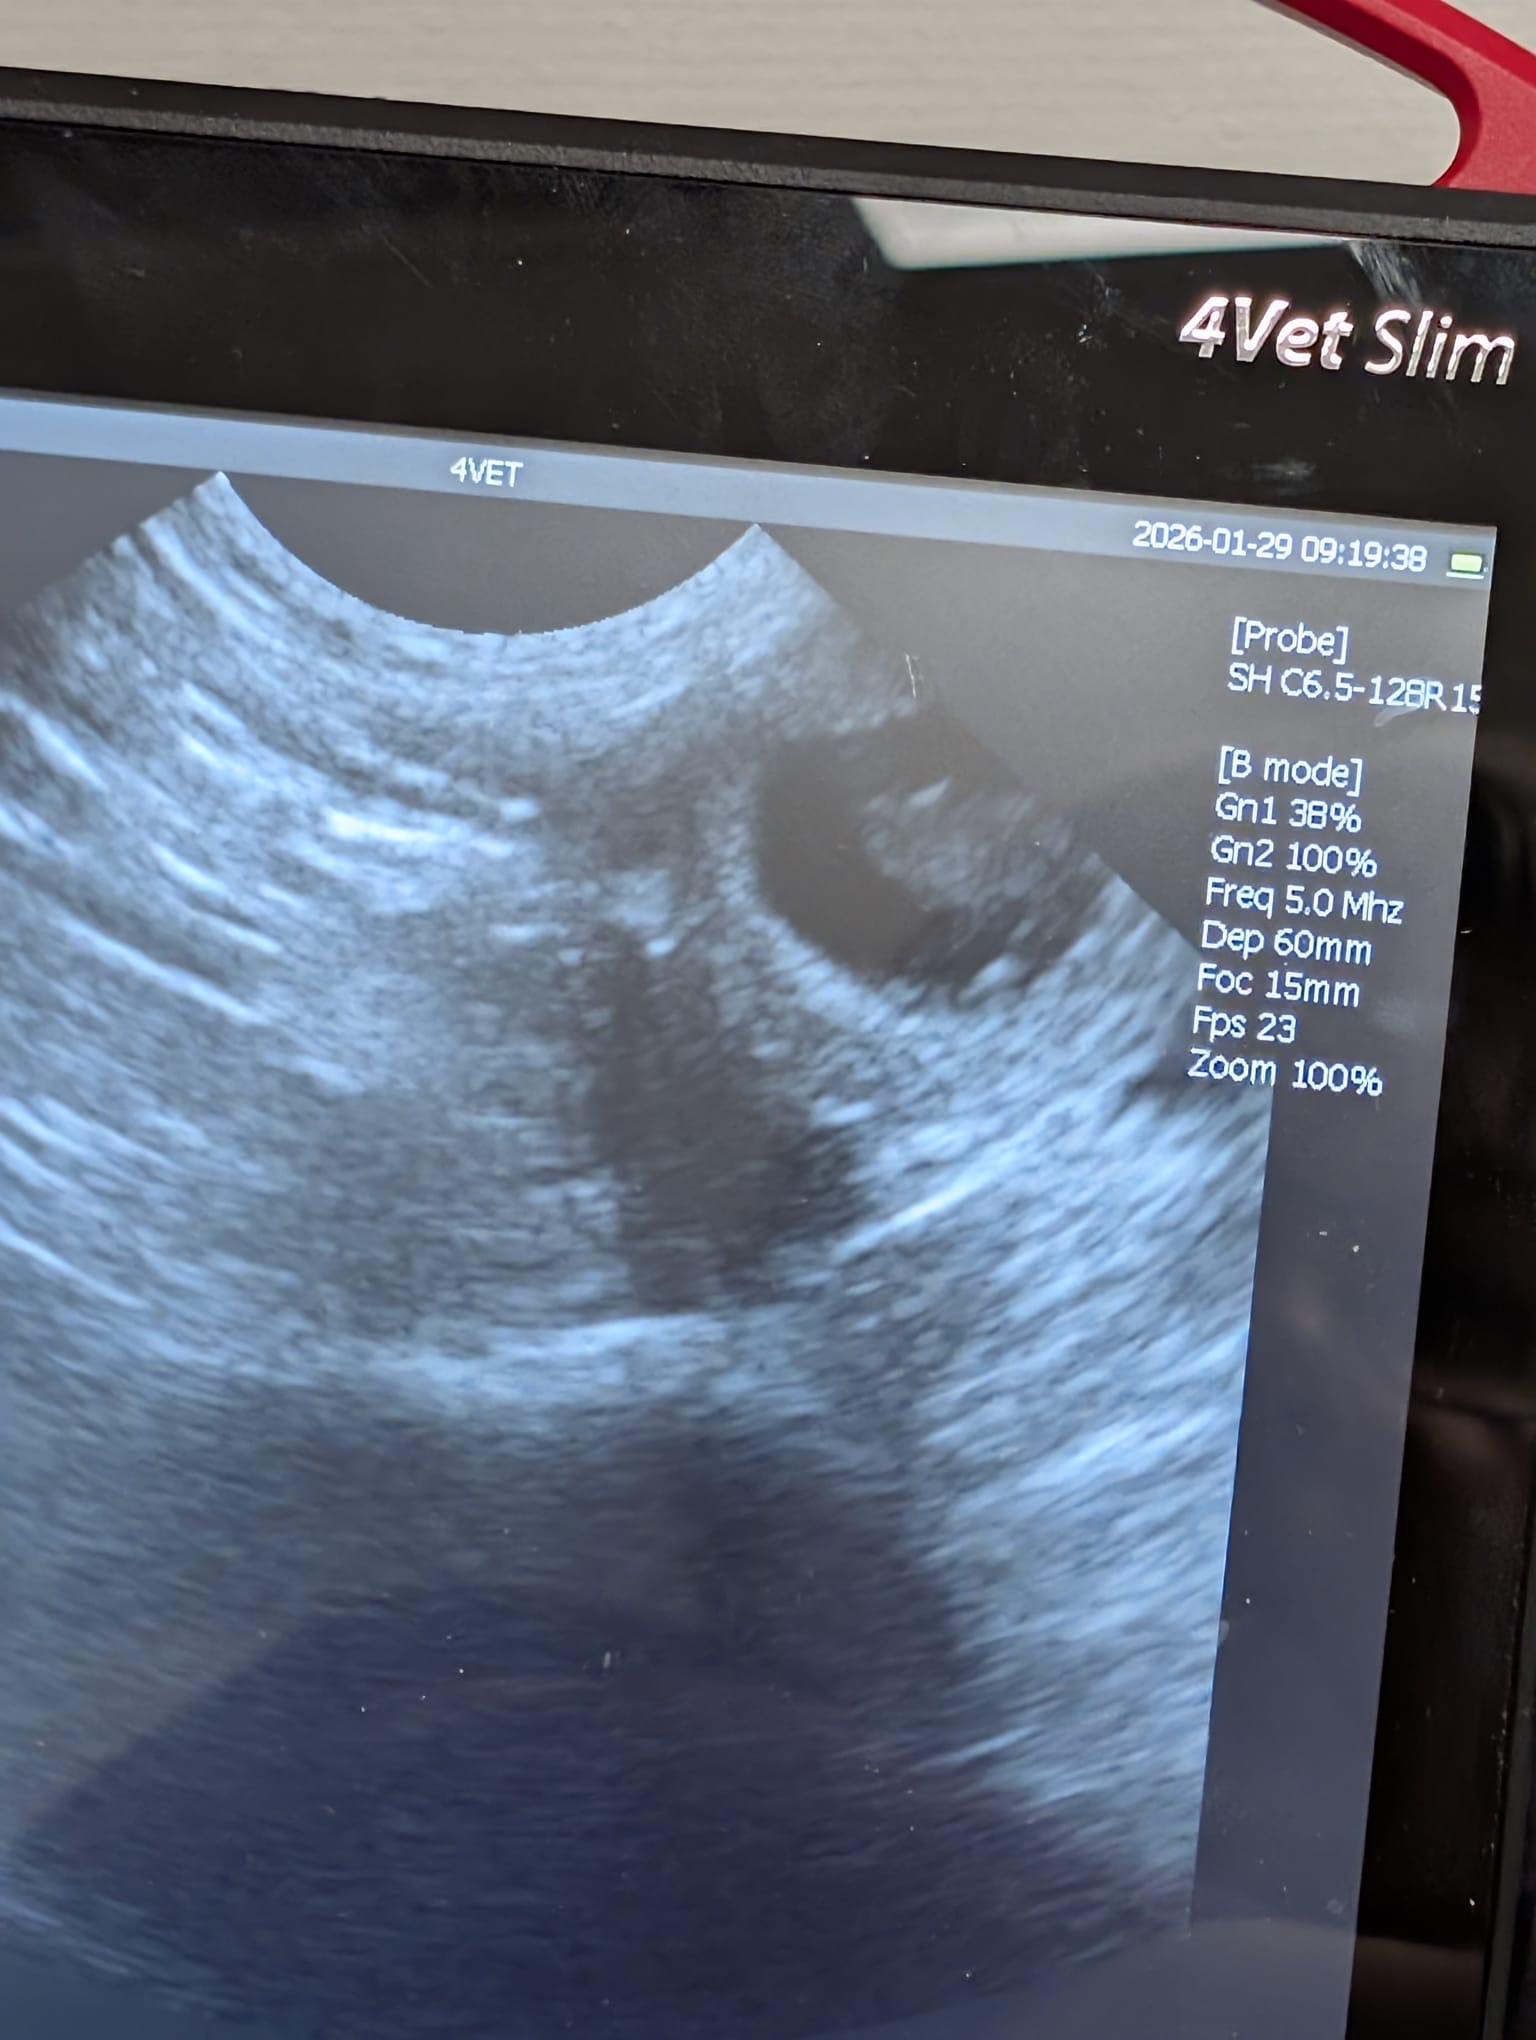

Beräknad födsel: runt 4/3

Beräknad födsel: 1/4